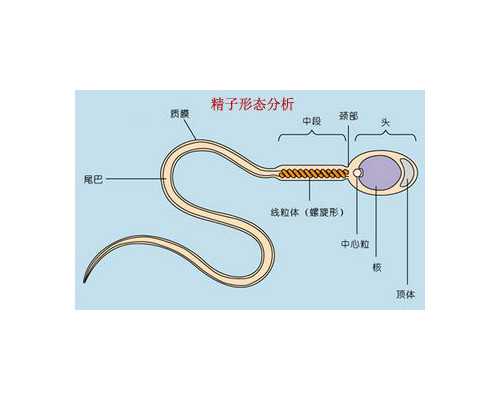

夫妻雙方的檢查主要是檢查夫妻雙方的生殖系統(tǒng),檢查內(nèi)容包括夫妻雙方的身體狀況和體內(nèi)激素水平,以判斷排卵、受精及受精后胚胎的發(fā)育情況。具體來說,夫妻雙方的檢查包括:男方檢查,主要是檢查精子質(zhì)量;女方檢查,主要是檢查卵子質(zhì)量和宮腔環(huán)境。此外,夫妻雙方還應(yīng)定期進行抗體檢查,以確保安全,同時還要檢查男方的精液,以確保精子的活力和數(shù)量。